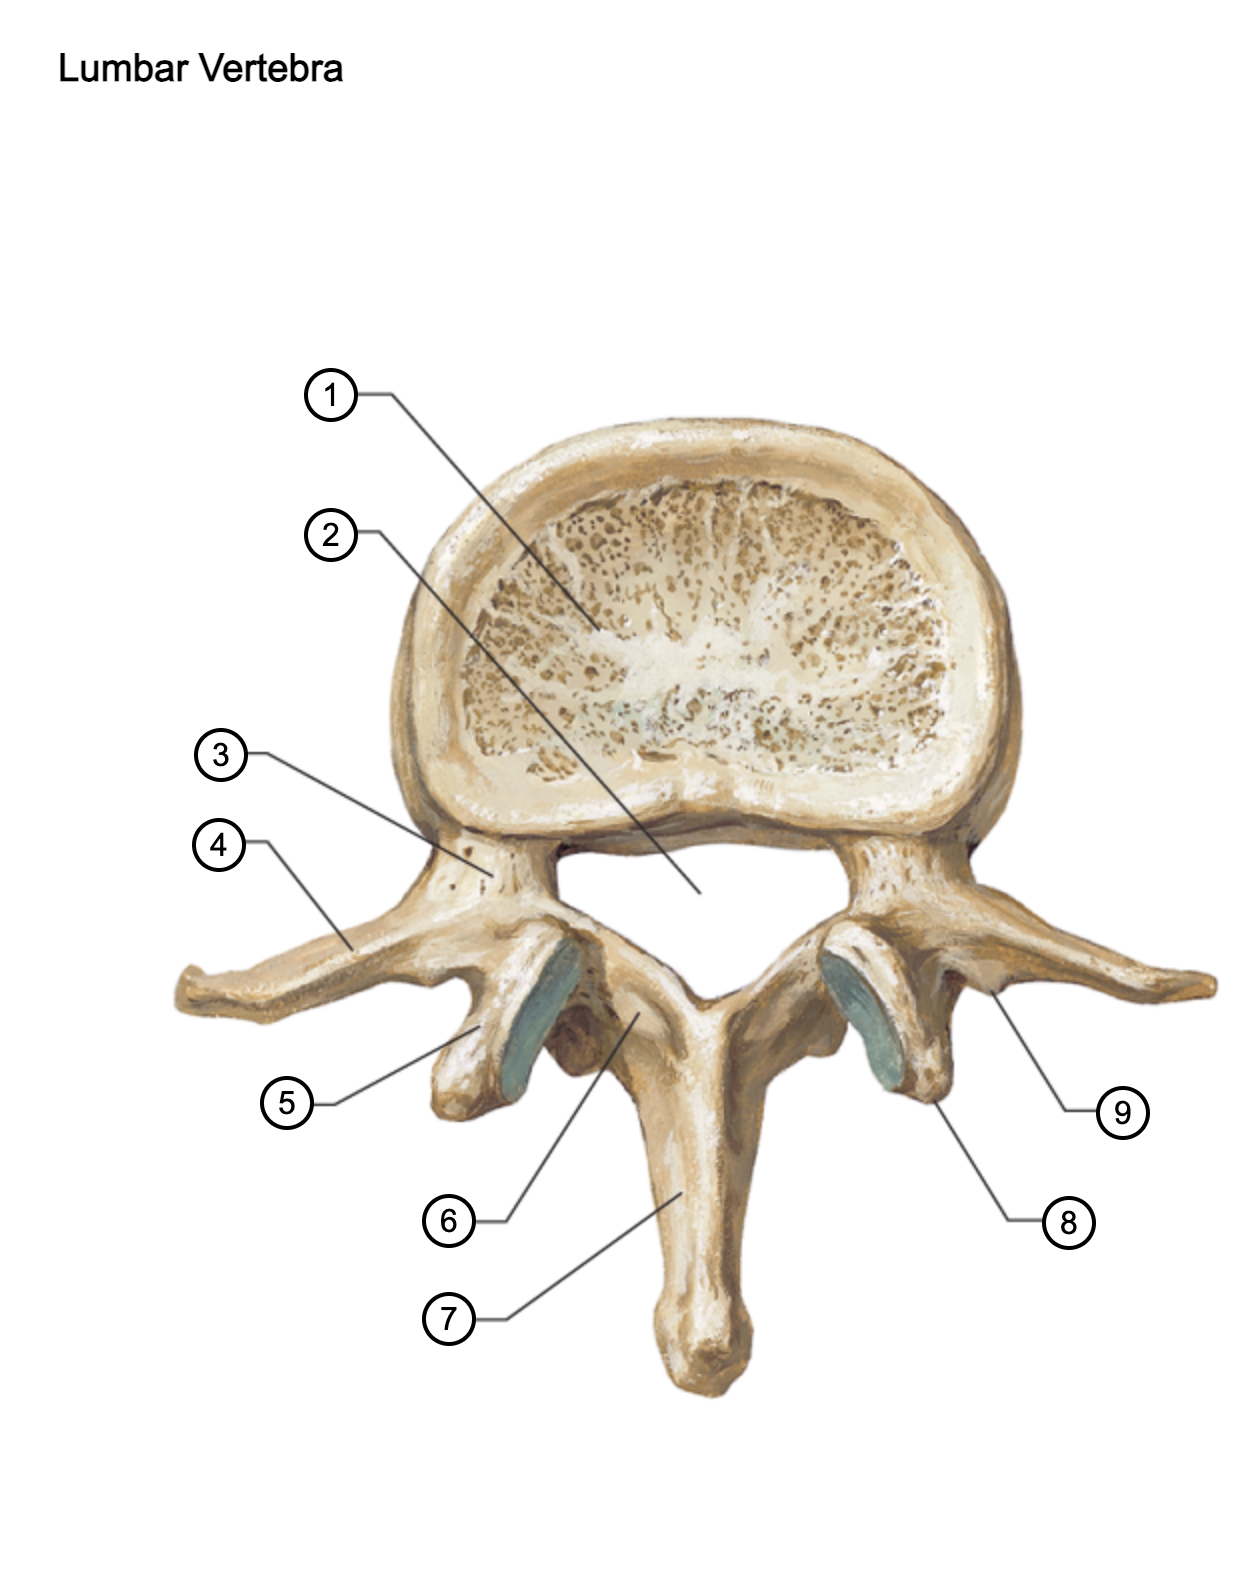

1

vertebral body

2

vertebral foramen

3

pedicle

4

transverse process

5

superior articular process

6

lamina

7

spinous process

8

mammillary process

9

accessory process